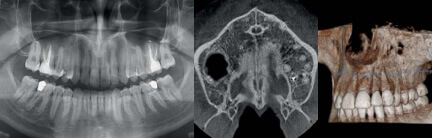

自由に設定できる撮影方法や領域によって、インプラントに重要な顎の骨の状態などを把握できます。また、3D(立体)による精密なシュミレーションや計画も可能なため、より正確なインプラント治療を実現します。